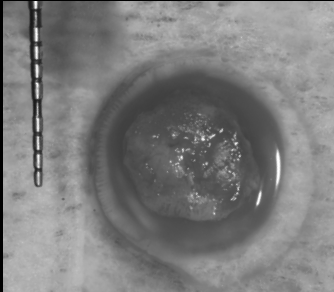

上唇の腫脹を認め、CT検査にて根尖部に嚢胞様透過像を認めた。左上の前歯が不自然に大きく噛み合わせが強くなっていたことがフレアアップの一因と考える。精密根管治療を行い、感染経路を遮断したのち歯根端切除術にて嚢胞を摘出した。

治療中

治療中